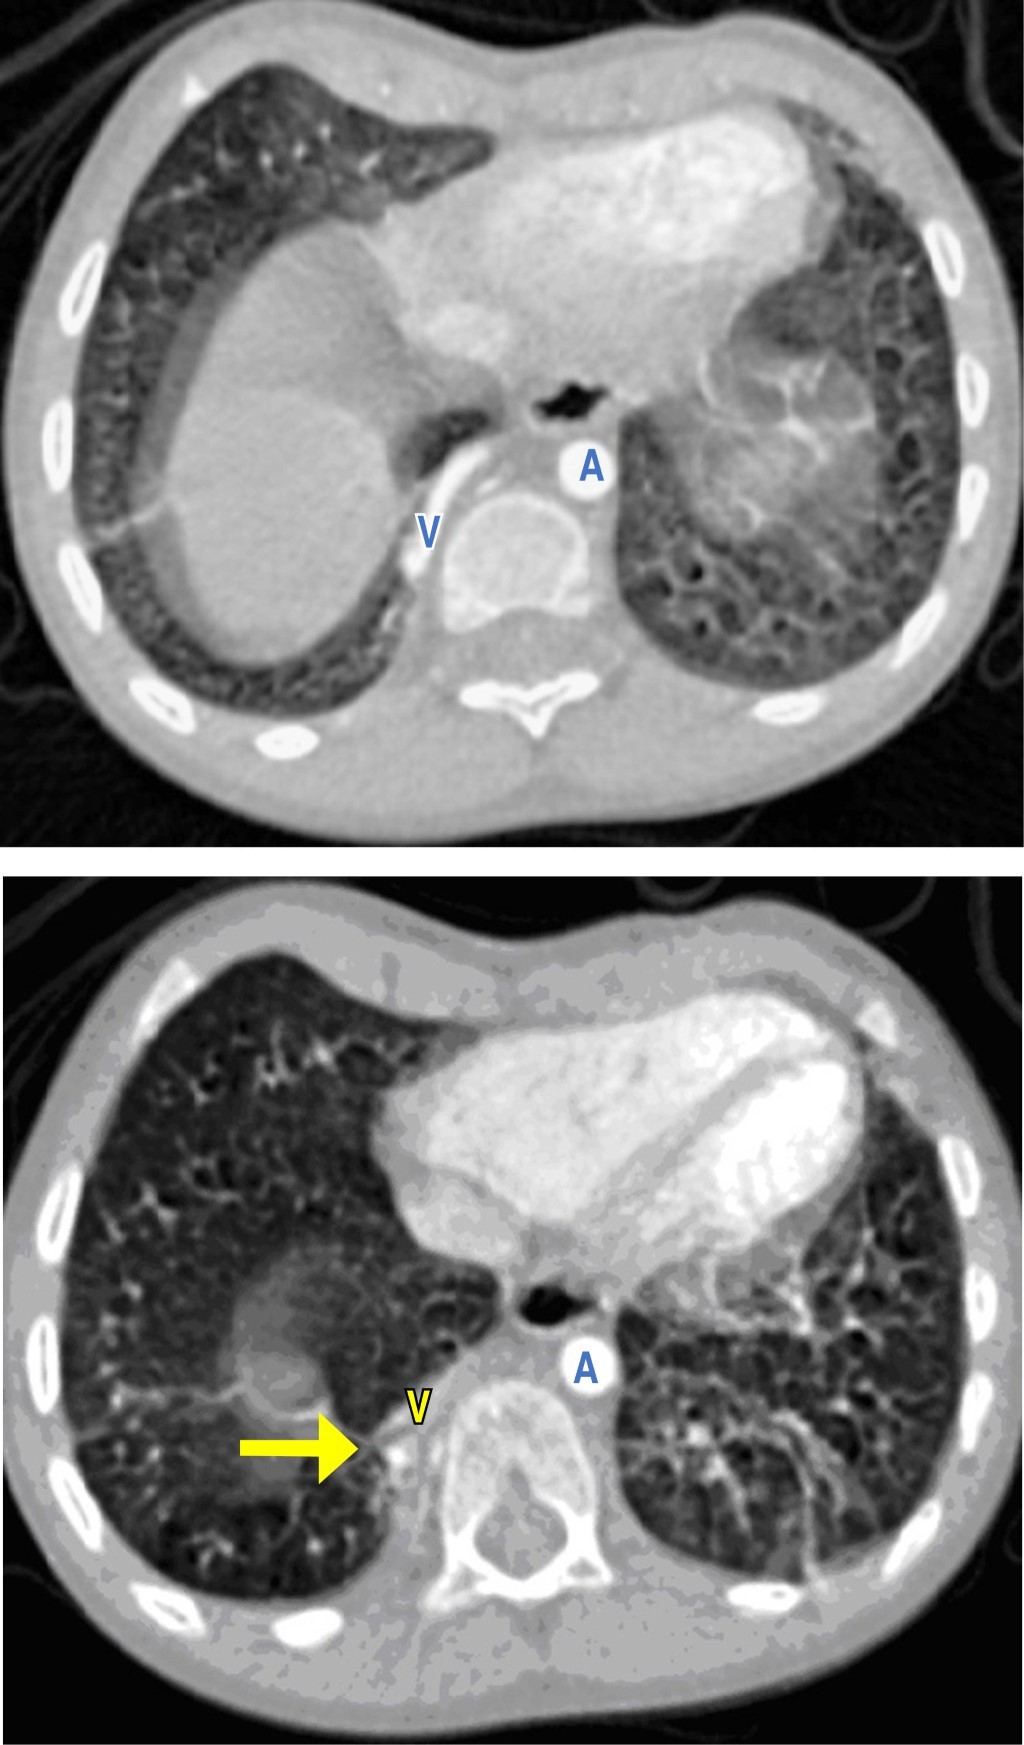

Estudios: difusión de monóxido de carbono (DLCO) 7.5 mL/min/mmHg (valor predicho 10.2), espirometría posbroncodilatador con una respuesta en volumen espiratorio forzado en el primer segundo (FEV1) del 16% y de más de 200 mL. La radiografía de tórax muestra un patrón atelectásico (Figura 1). Serie esofagogastroduodenal (SEGD) con presencia de reflujo grado III; en la angiotomografía de tórax (angio-TC) se observa una subclavia derecha aberrante (Figura 2), lo mismo que en la aorta descendente, también un vaso aberrante (Figuras 3 y 4).

Por otra parte, las técnicas de imagen son pruebas complementarias que confirmarán el diagnóstico. La radiografía de tórax puede proporcionar información sobre el desplazamiento del arco aórtico o la tráquea, la presencia de una estenosis traqueal, así como infiltraciones pulmonares, distelectasias o atelectasias como signos de compresión de las vías respiratorias.9 El esofagograma muestra la indentación esofágica; sin embargo, la información anatómica obtenida no es lo suficientemente precisa para el tratamiento terapéutico, por lo que se requieren imágenes transversales como la tomografía computarizada (TC) o la resonancia magnética (RM). Se pueden usar métodos de posprocesamiento para generar datos 3D, tanto de la TC como de la RM, dando una vista detallada de la morfología vascular.10 En cuanto a los estudios de radiología la SEGD no reveló identaciones esofágicas, sólo la presencia del reflujo severo; tampoco la tele de tórax mostró imágenes radiológicas sugerentes de las malformaciones, por lo que no fueron concluyentes para el diagnóstico. Por lo tanto, la TC de tórax y la angiotomografía son los estudios de elección para el diagnóstico de los anillos vasculares y de las malformaciones pulmonares como lo es el secuestro pulmonar intralobar o extralobar, la otra patología agregada en nuestro paciente.

En cuanto al secuestro pulmonar intralobar y su asociación con este síndrome no existe bibliografía a nivel mundial que los relacione en una entidad común. El secuestro pulmonar es una malformación congénita broncopulmonar poco frecuente caracterizado por un segmento anormal pulmonar irrigado por una arteria aberrante de origen sistémico, en 95% de los casos se ubica en el lóbulo inferior izquierdo, representan de 0.15-6.4% de todas las malformaciones pulmonares congénitas.11,12 La incidencia anual estimada es de 30 a 42 casos por 100,000 habitantes.13 Es frecuente que se asocien con otras anomalías congénitas como la hernia diafragmática o la cardiopatía congénita.14 Se clasifica en intralobar y extralobar de acuerdo con la ausencia o presencia de una cubierta de pleura visceral independiente en tejidos pulmonares anormales.12 El secuestro intralobar es más común, se presenta en 75% de los casos.13 Estas estadísticas hacen de este caso algo poco común, puesto que a pesar de que el secuestro pulmonar intralobar es más común, la localización derecha puede hacer más difícil su diagnóstico.

Los síntomas de esta enfermedad son atípicos y tienden a diagnosticarse erróneamente, los pacientes presentan cuadros repetitivos de neumonías. Se ha descrito neumotórax de repetición, bronquitis obstructiva y dolor torácico, aunque menos frecuentes.13 En las radiografías de tórax, el secuestro intralobar puede contener aire, suelen ser más heterogéneos y menos definidos y pueden imitar una neumonía o un absceso pulmonar. En las tomografías se puede observar una masa quística con contenido aéreo o líquido, enfisema focal e hipervascularización del tejido afectado.13 La presencia del vaso anómalo se demuestra con tomografía con contraste intravenoso en 72% de la aorta torácica descendente, de la aorta abdominal, el eje celíaco o la arteria esplénica (21%), arteria intercostal (3%) y rara vez a través del subclavio, torácica interna y arterias pericardiacofrénicas.15 Tal y como se ha mencionado, los estudios radiológicos son sumamente importantes y aunque la radiografía no fue concluyente para el diagnóstico de este caso, la angio-TC sí lo fue acorde a lo que marca la literatura, en donde se observó un aumento en la hipervascularización, así como la presencia de un vaso anómalo de la aorta torácica descendente. El tratamiento de consenso para los secuestros intralobares y extralobares es la remoción quirúrgica.11-15 Este paciente se encuentra en espera para realizarle embolización por cateterismo cardíaco con un dispositivo oclusor.